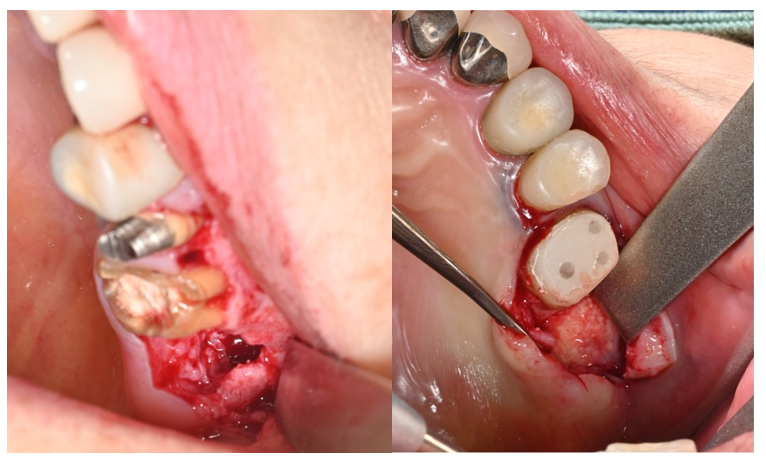

インプラント症例4

治療前

骨造成

治療後

| 治療内容 | 骨吸収が大きかったため、まず骨造成を行い、6か月後にインプラント埋入(ソケットリフト併用)を行った。 埋入後3か月後に上部構造(ジルコニア)を装着した。 |

| 治療期間 |

1年・15回 |

| 治療費用 | 総額:605,000円(税込) 【内容】 骨造成(GBR) 100,000円 インプラント埋入手術 270,000円 ソケットリフト 50,000円 インプラント被せ物 130,000円 |

| リスク・副作用 | ・外科処置が2回必要。 ・自費診療(保険適用外)となる。 ・骨造成後、腫れや内出血が起こる可能性がある。 ・ソケットリフト後、稀に上顎洞内感染の可能性がある。 |